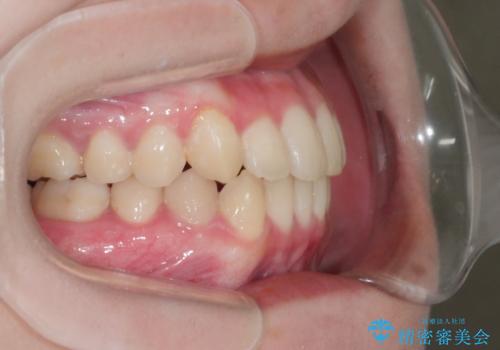

八重歯とクロスバイト:インビザライン治療

- 八重歯が気になるとの事でご相談にいらした方です。

インビザラインで綺麗に並べました。

気になっていた八重歯が綺麗になって大変喜んでいただけました。